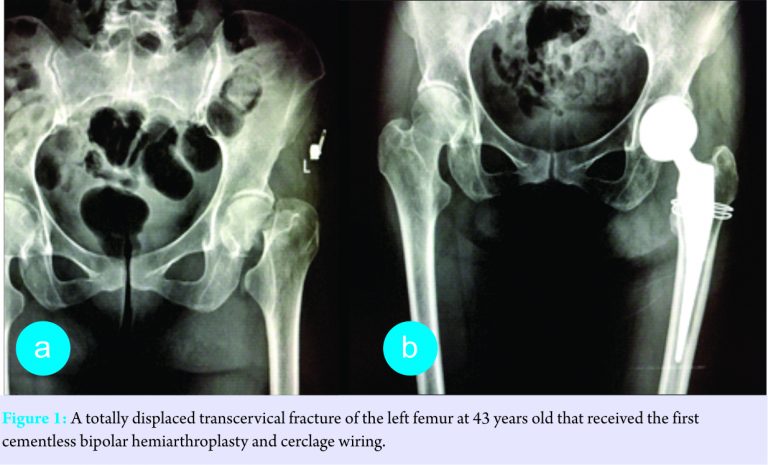

A single 46-year-old Thai woman presented with acute right hip pain after falling onto the ground and could not bear weight. Her underlying diseases were hypertension and mild intellectual disability (IQ=60). At the age of ten, she developed bilateral cataracts and underwent bilateral intraocular lens replacement at the age of about 20. Thereafter, a painless mass gradually developed at the medial side of the left foot and both Achilles tendons became enlarged. At the age of 43, she sustained a left femoral neck fracture owing to a fall in her home and underwent hip hemiarthroplasty (Fig. 1a and b). Her ambulatory status was household independence. A physical examination revealed a thin woman (height 153 cm, weight 38 kg) with her right lower limb in the external rotation position. The left posterior tibial tendon insertion and both Achilles tendons were enlarged in irregular shapes (Fig. 2 a-c). Pes cavus in both feet and camptodactyly of her left little finger were observed. The hip radiographs showed a complete, totally displaced, transcervical fracture of the right femur, Garden classification Type 4 (Fig. 3). The proximal femur appearance was categorized as Dorr Type B. Retention of the well-fixed cementless bipolar prosthesis in the left hip was found. Other bone-surveying radiographs of spine, pelvis, and femurs revealed generalized osteopenia. She underwent hip hemiarthroplasty using a posterolateral approach and a cementless bipolar prosthesis (Avenir Muller stem, Zimmer, Switzerland). There was an accidental crack of the calcar femorale during the stem insertion. A loop of cerclage wiring was then added to prevent fracture propagation. The posterior capsule and short external rotators were repaired. The operative record of the left hip hemiarthroplasty also noted a calcar femorale fracture during the prosthesis insertion warranting cerclage wiring. Cementless bipolar prosthesis (Modular Taperloc stem, Biomet, USA) had been implanted through a posterolateral approach.

She was prescribed oral calcium carbonate with Vitamin D2 for osteoporotic prophylaxis and allowed partial weight bearing for 6 weeks. The hip radiographs at the latest follow-up (post-operative 7 and 41 months for right and left hips, respectively) showed well-fixed and well-aligned femoral prostheses (Fig. 5a-c).The right leg was found to be 5 mm shorter. A CT scan of both hips and femurs demonstrated 12° and 15° anteversion of right and left femoral stems, respectively. The native acetabular anteversion was 23°. She occasionally had slight pain in both hips but no compromise in activity. She could stand without support and walk with a slight limp for 10–15 minutes. She was capable of going up or down stairs with handrails. Both hip joints had a full range of movement with Harris hip scores of 81 points equally.